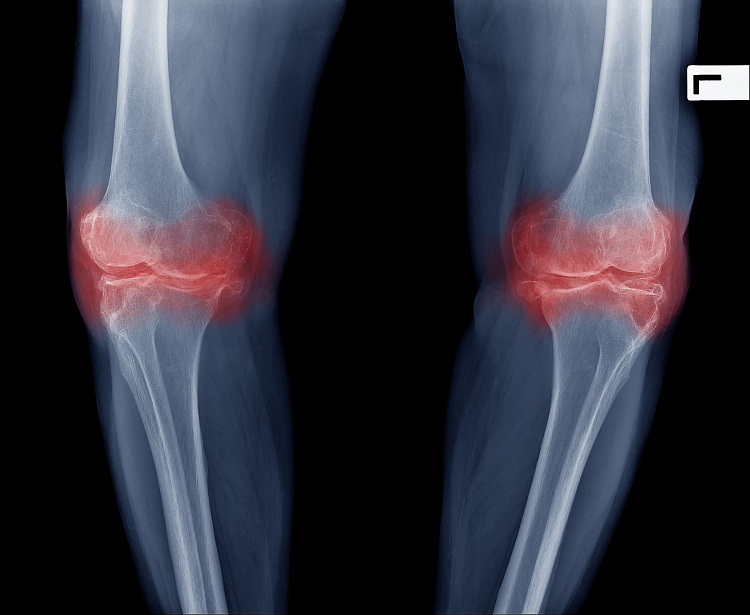

Артроз коленного сустава

Патологические процессы в области хряща бывают представлены не только артрозом, но и деформирующим остеоартрозом. Это недомогание, в основном, характерно для людей старше 45-50 лет, однако в последнее время встречается и среди молодежи. По статистике, артроз коленного сустава диагностируется почти так же часто, как коксартроз и нарушения в работе межпозвоночных суставов. Первичная форма заболевания не имеет явных причин. Вторичная всегда обусловлена каким-либо фактором риска. Среди спортсменов и грузчиков она встречается наиболее часто, что связано с особенностями их физических нагрузок.

Симптомы артроза коленного сустава

Интенсивность проявлений заболевания зависит от степени его тяжести. К примеру, хруст и щелканье поначалу не сильно беспокоят, мало кто подозревает, что у артроза коленного сустава симптомы могут быть такими. Но со временем эти проявления усиливаются и приводят к более серьезным нарушениям. Поэтому нужно обязательно записаться на прием к врачу, если:

Причины артроза колена

Вторичная форма заболевания отличается более агрессивной формой. Факторы, вызывающие ее, хорошо известны врачам. Так артроз коленного сустава возникает по следующим причинам:

В норме суставный хрящ разрушается со временем. Это связано с естественным процессом старения. Обычно процесс начинается в возрасте от 40 до 50 лет. Но если у больного наблюдается деформирующий артроз коленного сустава, то первые проявления начинают беспокоить еще в юности. Точно поставить диагноз в таком возрасте может только врач после осмотра и назначения ряда обследований. Кроме того, сегодня узнать предполагаемую причину болезни стало проще — в Интернете появились сайты самодиагностики.

Какой врач лечит артроз коленного сустава? Этот вопрос, который встает практически перед каждым из тех, кто столкнулся с этим заболеванием. В этой ситуации хочется получить квалифицированную помощь профессионала в своей области. Для того, чтобы его найти, необходимо четко представлять, врач какой специализации лечит эту патологию.

Артроз сустава колена — хроническая болезнь, главным признаком которой выступает истончение и постепенное разрушение хряща, что вызывает деформацию сустава и нарушение его функции. Гонартроз, как еще называют патологию, разделяется на несколько групп по степени тяжести. Основными проявлениями болезни являются следующие явления:

Причиной возникновения гонартроза выступают разные факторы, включая следующие:

Пожилой возраст тоже может выступать причиной возникновения болезни, поскольку со временем суставная структура изнашивается и не выдерживает нагрузок, с которыми справлялась раньше.

Для справки! Гонартроз чаще наблюдается у женщин и обусловлен сочетанием лишнего веса с варикозом.

Симптомы и лечение патологии взаимосвязаны и зависят от степени развития гонартроза.

Боли незначительны и появляются при активных движениях. Но в состоянии покоя болевые ощущения отступают. Внешней суставной деформации не наблюдается, хотя отмечается повреждение хрящевой ткани.

В данной ситуации щель сустава сужается, а хрящ повреждается, чем объясняются сильная боль при движении колена. На этой стадии болезни возникает характерный хруст, которым сопровождается сгиб ноги.

Сгибательно-разгибательные движения колена понемногу становятся невозможными.

Наиболее тяжелая форма, при которой болевые ощущения наблюдаются как в покое, так и при движениях. Это обусловлено полным истончением хрящевой ткани. Локально кость колена может быть абсолютно обнажена.